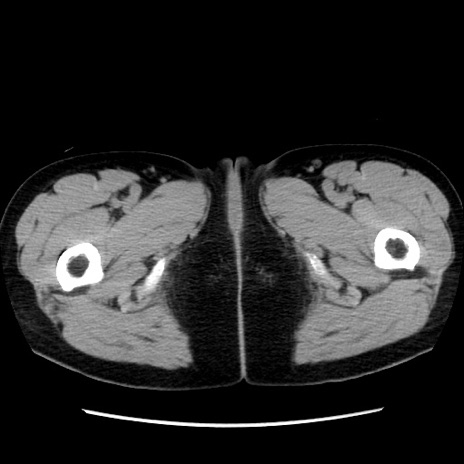

症例10(横断像)

【症例】 50歳代女性

【主訴】 腹痛

【現病歴】前日生レバーを食べた。今朝に排便あり。 昼前に突然発症の腹痛を生じ、当院救急外来を受診した。

【既往歴】 子宮筋腫にてで子宮全摘後

【身体所見】 意識清明、腹部:平坦、軟、下腹部やや左を中心に圧痛・反跳痛あり、筋性防御あり

【データ】WBC 7800、CRP 0.07